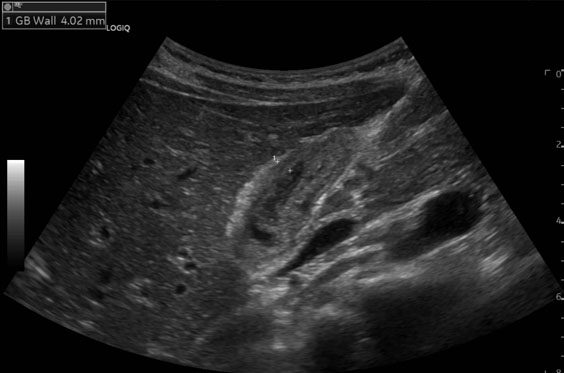

Jejunal diverticulosis (JD) is an uncommon and often underdiagnosed condition, usually discovered incidentally and rarely associated with acute complications such as diverticulitis, obstruction, abscess, perforation, or fistula formation. However, when complications do occur, they can be severe and diagnostically challenging. We present the case of a 75-year-old Female who arrived with an acute-onset abdominal pain with progressive distension and persistent vomiting. Computed tomography (CT) revealed a small bowel obstruction due to an enterolith. Emergency laparotomy revealed a small bowel obstruction at mid ileum due to an enterolith as well as an omental band adhered to the inflamed jejunal diverticulum proximally resulting in a closed loop in the affected segment of small bowel. The omental band was divided and the enterolith was removed via an enterotomy without requiring a small bowel resection. The patient was managed with antibiotics postoperatively and she made an unremarkable recovery. Closed loop small bowel obstruction as a result of complicated jejunal diverticular disease is rare in the literature and it highlights the critical importance of maintaining a high index of suspicion, particularly in older patients presenting with acute abdomen.